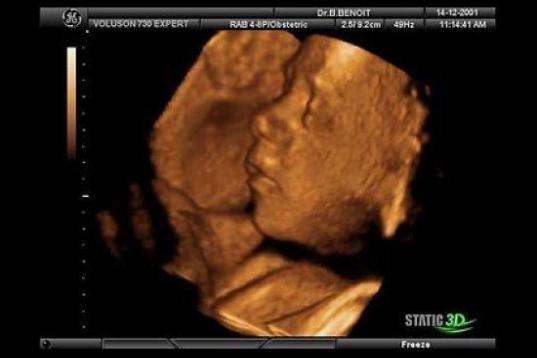

En esta galería puedes ver en fotos como es el desarrollo de un feto de semana en semana:

Desarrollo del feto, en fotos

Ver la galería